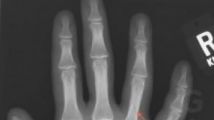

Nos confrères de Gizmodo.fr ont relevé une bien curieuse news insolite le 3 avril dernier.Un médecin leur a en effet fait parvenir une radio d'une main d'un de ses patients, avec un doigt fracturé (voir les flèches en rouge). Rien de bien incroyable à ce stade, sauf que la main en question appartient à un joueur, qui s'est fracturé le doigt, nous dit-on, en jouant à God of War III. les explications du médecin s'imposent :

L'un de mes patients était tellement pris dans God of War III qu'il a roulé sur sa main avec son genou et s'est fracturé deux doigts. Ci joint sa radio (sans les informations personnelles et avec des flèches pour indiquer les fractures). C'est la première fois que je vois une blessure aussi grave causée par le jeu vidéo.